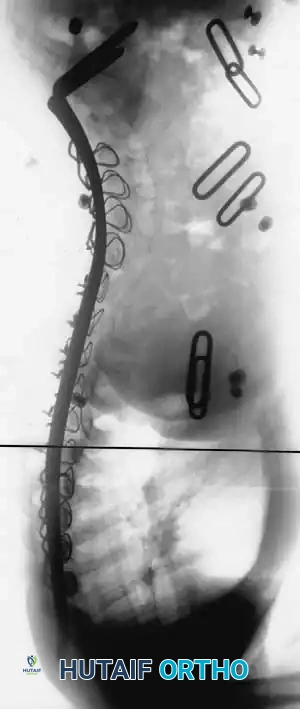

3. Instrumentation Strategies

Due to poor bone stock, multiple points of fixation are required to distribute corrective forces.

* Segmental Instrumentation: The gold standard involves rigid rod constructs (e.g., Cotrel-Dubousset principles) utilizing pedicle screws, hooks, and sublaminar wires or cables.

* Sublaminar Wires/Cables: Techniques pioneered by Luque remain highly relevant in neuromuscular scoliosis. Sublaminar cables provide excellent pull-out strength in osteopenic bone and distribute translational forces evenly across the apex of the deformity.

Associated Surgical & Radiographic Imaging

Hutaifortho's Orthopaedic Diagram